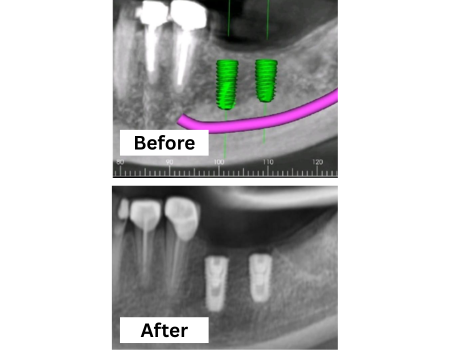

Dental Implants Treatment

Permanent, natural-looking tooth replacements that restore function and aesthetics, improving chewing, confidence, and long-term oral health.